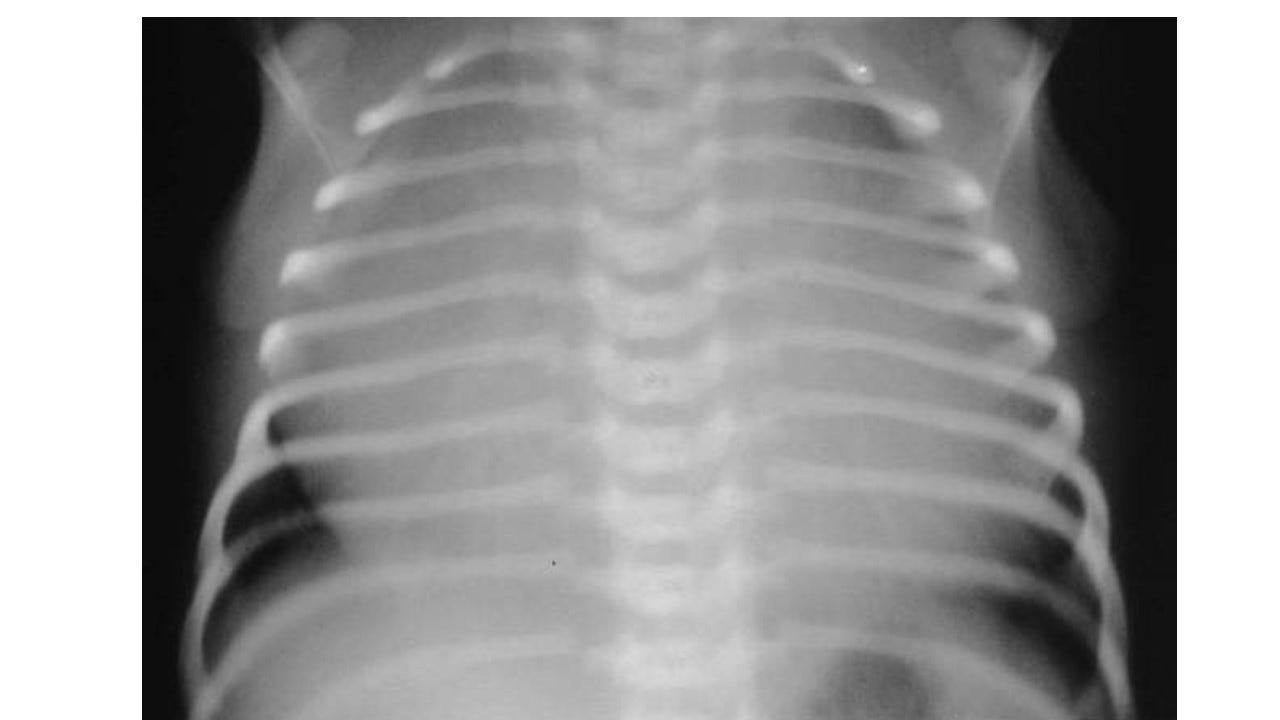

The Xray of Severe Neonatal Ebstein’s will look like the following: